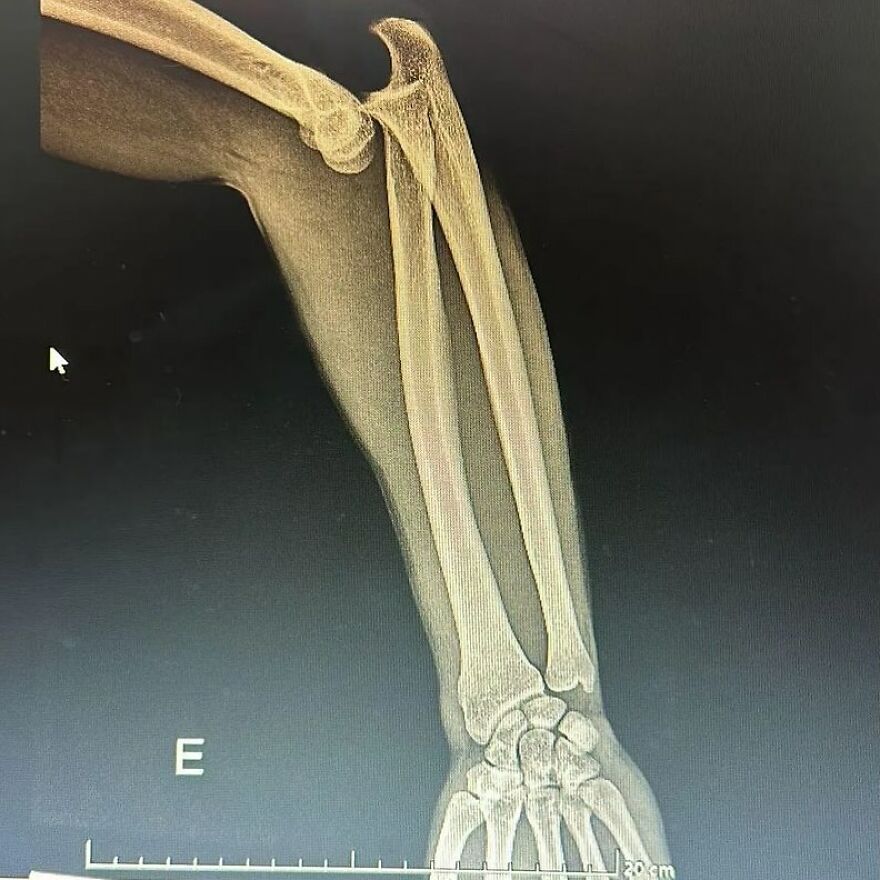

A dodgeball injury that resulted in radius and ulnar shaft fracture, aka broken forearm!

This sustained dodgeball injury has led to a bilateral diaphyseal fracture involving both the radius and ulnar shaft, thereby presenting as a fracture of the forearm.

This particular injury entails the disruptive discontinuity of the long bones situated within the antebrachial region, namely the radius and ulnar diaphyses.